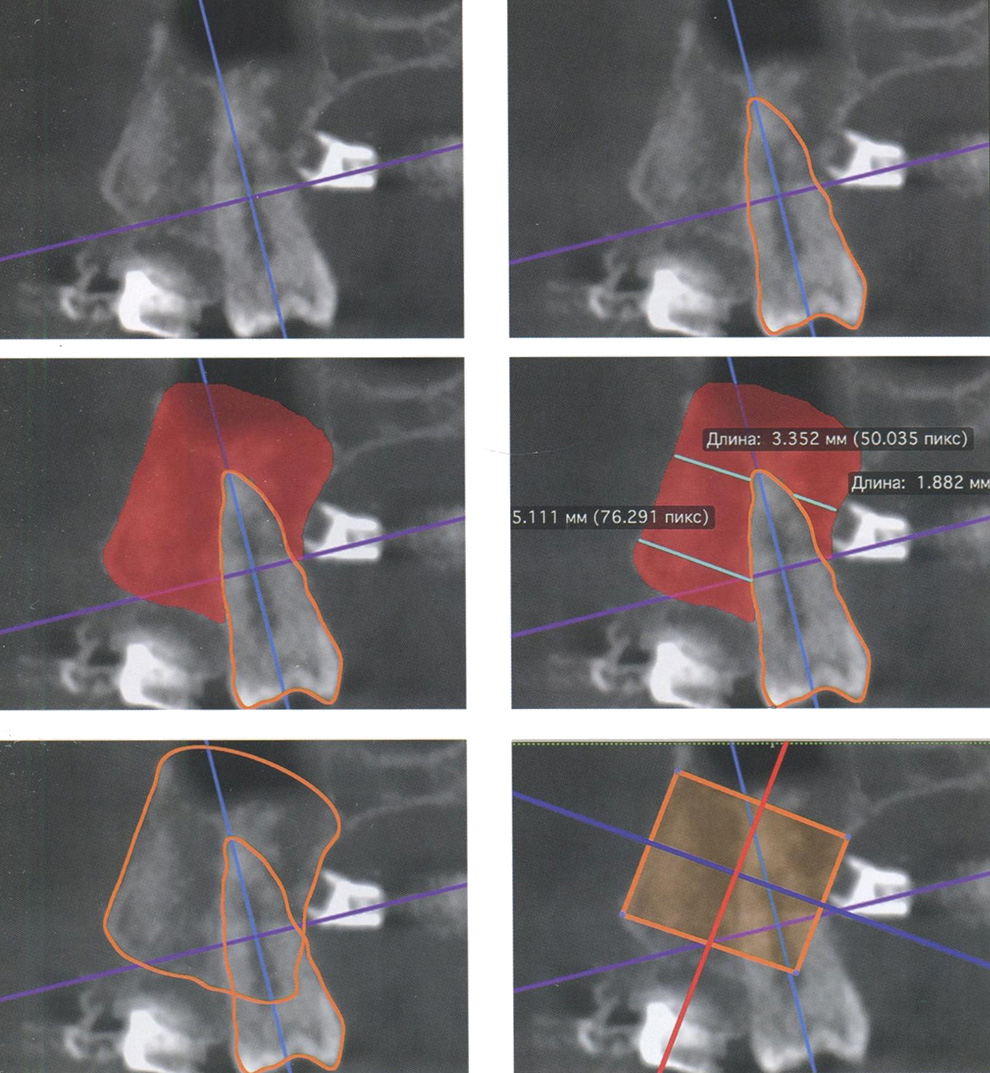

1) длину и форму корней зубов (рис. 76);

Оценка длины и формы корня зуба

Рис. 76. Оценка длины и формы корня зуба 2.1 на сагиттальных срезах компьютерных томограмм в окне мультипланарной реконструкции

2) положение ретинированных и дистопированных зубов, а также сверхкомплектных зубов (рис. 77);

Оценка положения ретинированного зуба

Рис. 77. Оценка положения ретинированного зуба 2.3 на компьютерных томограммах: а — окно объемного рендеринга; б — окно мультипланарной реконструкции

С целью оценки положения зубов на компьютерных томограммах по-явилась возможность проводить линейные измерения внутри альвеолярного(-ой) отростка/части челюстей, тем самым определять границы возможных перемещений (рис. 81).

Оценка положения резцов на компьютерных томограммах с помощью линейных параметров

Рис. 81. Оценка положения резцов на компьютерных томограммах с помощью линейных параметров между альвеолярным отростком верхней челюсти и корнем зуба 2.1 в области апексов, на уровне середины корня и гребне альвеолярного отростка

С усовершенствованием метода угловых измерений фронтальной группы зубов на компьютерных томограммах появилась возможность четкой визуализации оси каждого зуба (рис. 82).

На компьютерных томограммах стало возможным проводить анализ положения корней зубов боковой группы, каждого в отдельности, с помощью как линейных, так и угловых параметров (рис. 83). Среди угловых измерений отдельных зубов можно сопоставить ось отдельного зуба с осью альвеолярного(-ой) отростка/части исследуемого зубочелюстного сегмента (рис. 84).

Оценка положения зуба 2.1 с помощью углового параметра на компьютерных томограммах в окне мультипланарной реконструкции

Рис. 82. Оценка положения зуба 2.1 с помощью углового параметра на компьютерных томограммах в окне мультипланарной реконструкции

Оценка положения зуба

Рис. 83. Оценка положения зуба 1.6 на компьютерных томограммах с помощью: а — углового параметра /_u6/JJ; б — линейных параметров между альвеолярным отростком верхней челюсти и корнем зуба в области апексов, на уровне фуркации и гребне альвеолярного отростка

Методология проведения измерений по компьютерным томограммам

Рис. 84. Оценка положения зуба 1.5 на компьютерных томограммах с помощью линейных и углового параметров внутри альвеолярного отростка верхней челюсти